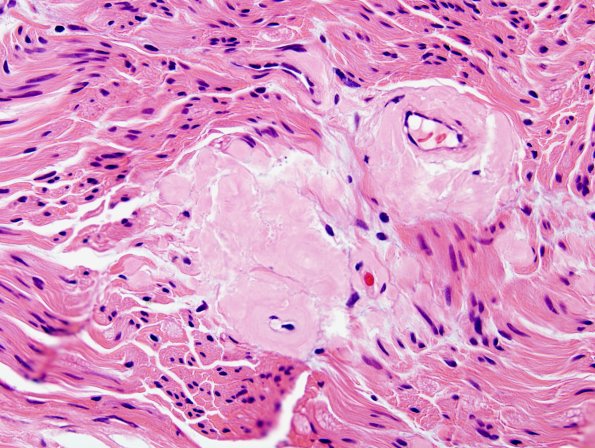

Washington University Experience | PERIPHERAL NEUROPATHY | 14 AMYLOID NEUROPATHY | 2A3 Amyloid Neuropathy (Case 2) H&E 2

Higher magnification demonstrates the solid material in this case which is much different from the wispy collections of delicate processes in Renaut bodies. (H&E)